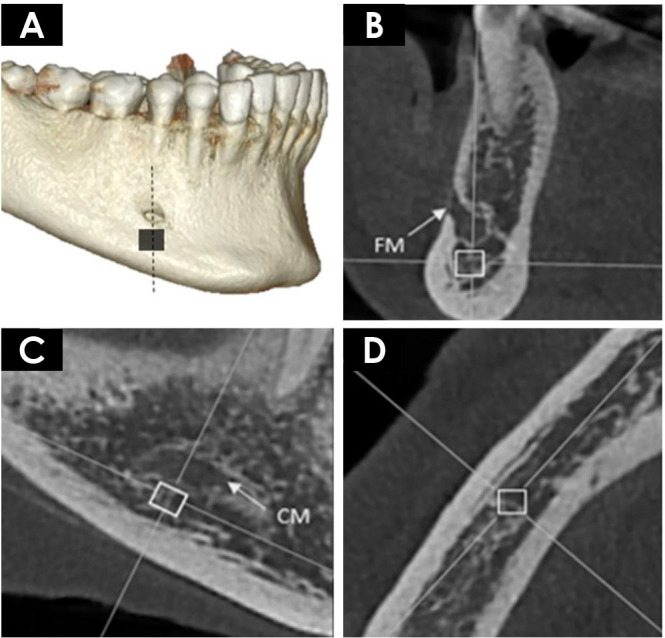

Purpose: This study aimed to evaluate the influence of different cone-beam computed tomography (CBCT) image reconstruction parameters (slice thickness, noise filter application and orthogonal plane) on the calculation of bone fractal dimension and, based on those findings, to determine the optimal protocol for this type of assessment.

Materials and methods: The sample consisted of 18 patients who underwent CBCT scans of the mandible and bone densitometry examinations. Four mandibular regions of interest were selected from the scans, with various image reconstruction parameters applied. Fractal dimension was calculated using the box-counting method. Two independent observers performed the evaluations, and all analyses were conducted with a significance level of 5%.

Results: The retromolar triangle and mandibular body regions did not demonstrate statistically significant differences when different tomographic reconstruction parameters were applied (P>0.05). The mandibular base did not display a consistent pattern that could define the influence of these parameters on its evaluation. The symphysis region showed improved performance in fractal analysis when using sagittal plane images with a 1 mm slice thickness.